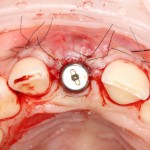

Все началось с воспаления, свищевого хода и удаления зуба:

Затем, мы готовим лунку и проверяем позиционирование импланта:

После чего аугментируем лунку. Для упаковки Bio-Oss Collagen очень удобно использовать аналоги имплантов:

Устанавливаем имплантат XiVE (Dentsply Implants):

Сразу на имплантат — временная коронка:

которая через три месяца, к моменту интеграции импланта, выглядит совсем иначе:

Ну и… к моменту установки постоянной коронки, у нас сохранился естественный контур прилегающей десны.